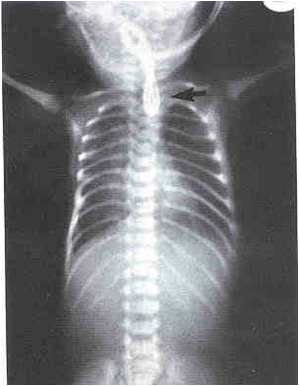

1.从口鼻插入F8号导尿管受阻,不能进入胃内。

2.颈、胸、腹正侧位X线摄片示导管卷曲或造影显示食道近端盲袋。